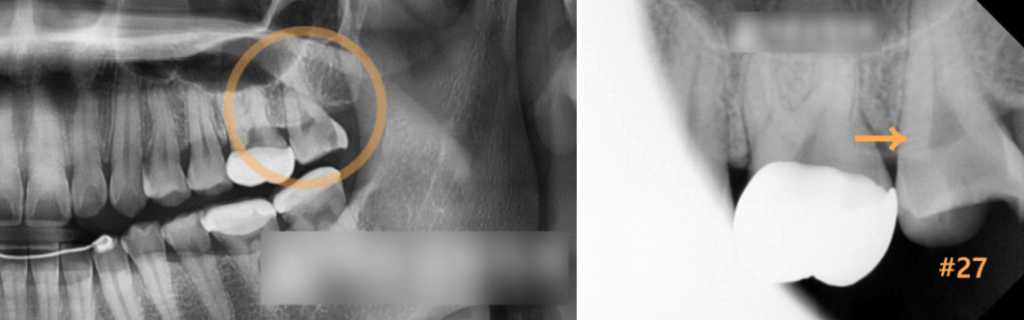

충치는 감염 범위에 따라 치료 방법이 달라지기에

방사선 촬영본을 통해 어디까지 퍼졌는지

자세하게 관찰해보겠습니다.

이미 치수강 근처까지 심하게 썩어 있는

맨 안쪽 치아를 확인할 수 있습니다.

아무래도 신경치료를 진행하여

감염된 근관을 제거하고

새로운 충전재로 채워 넣은 뒤

크라운을 씌워야할 것으로 보여집니다.